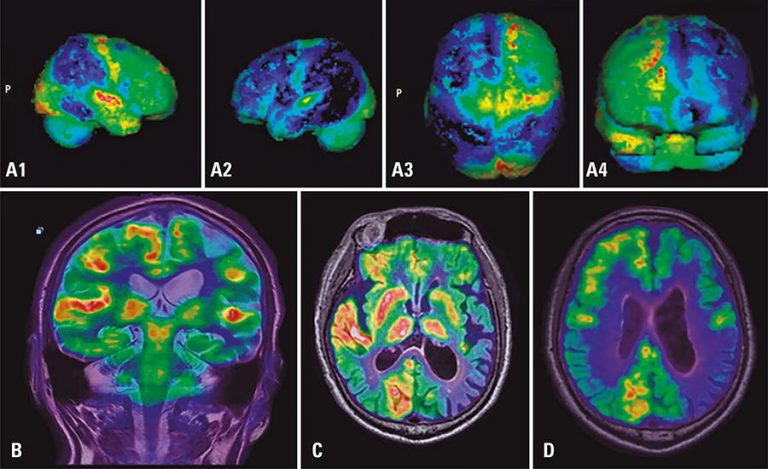

ABSTRACT In recent years, medical imaging with hybrid techniques has widely accepted and employed in clinical routine. PET/MRI offers significant advantages, including excellent contrast and resolution and reduced ionizing radiation, as compared to well-established PET/CT. Therefore, PET/MRI is a promising modality for oncologic imaging of some regions, such as brain, head and neck, liver and pelvis. This article set out to analyze clinical conditions that could benefit from PET/MRI imaging based on our caseload. The potential of PET/MRI to become […]